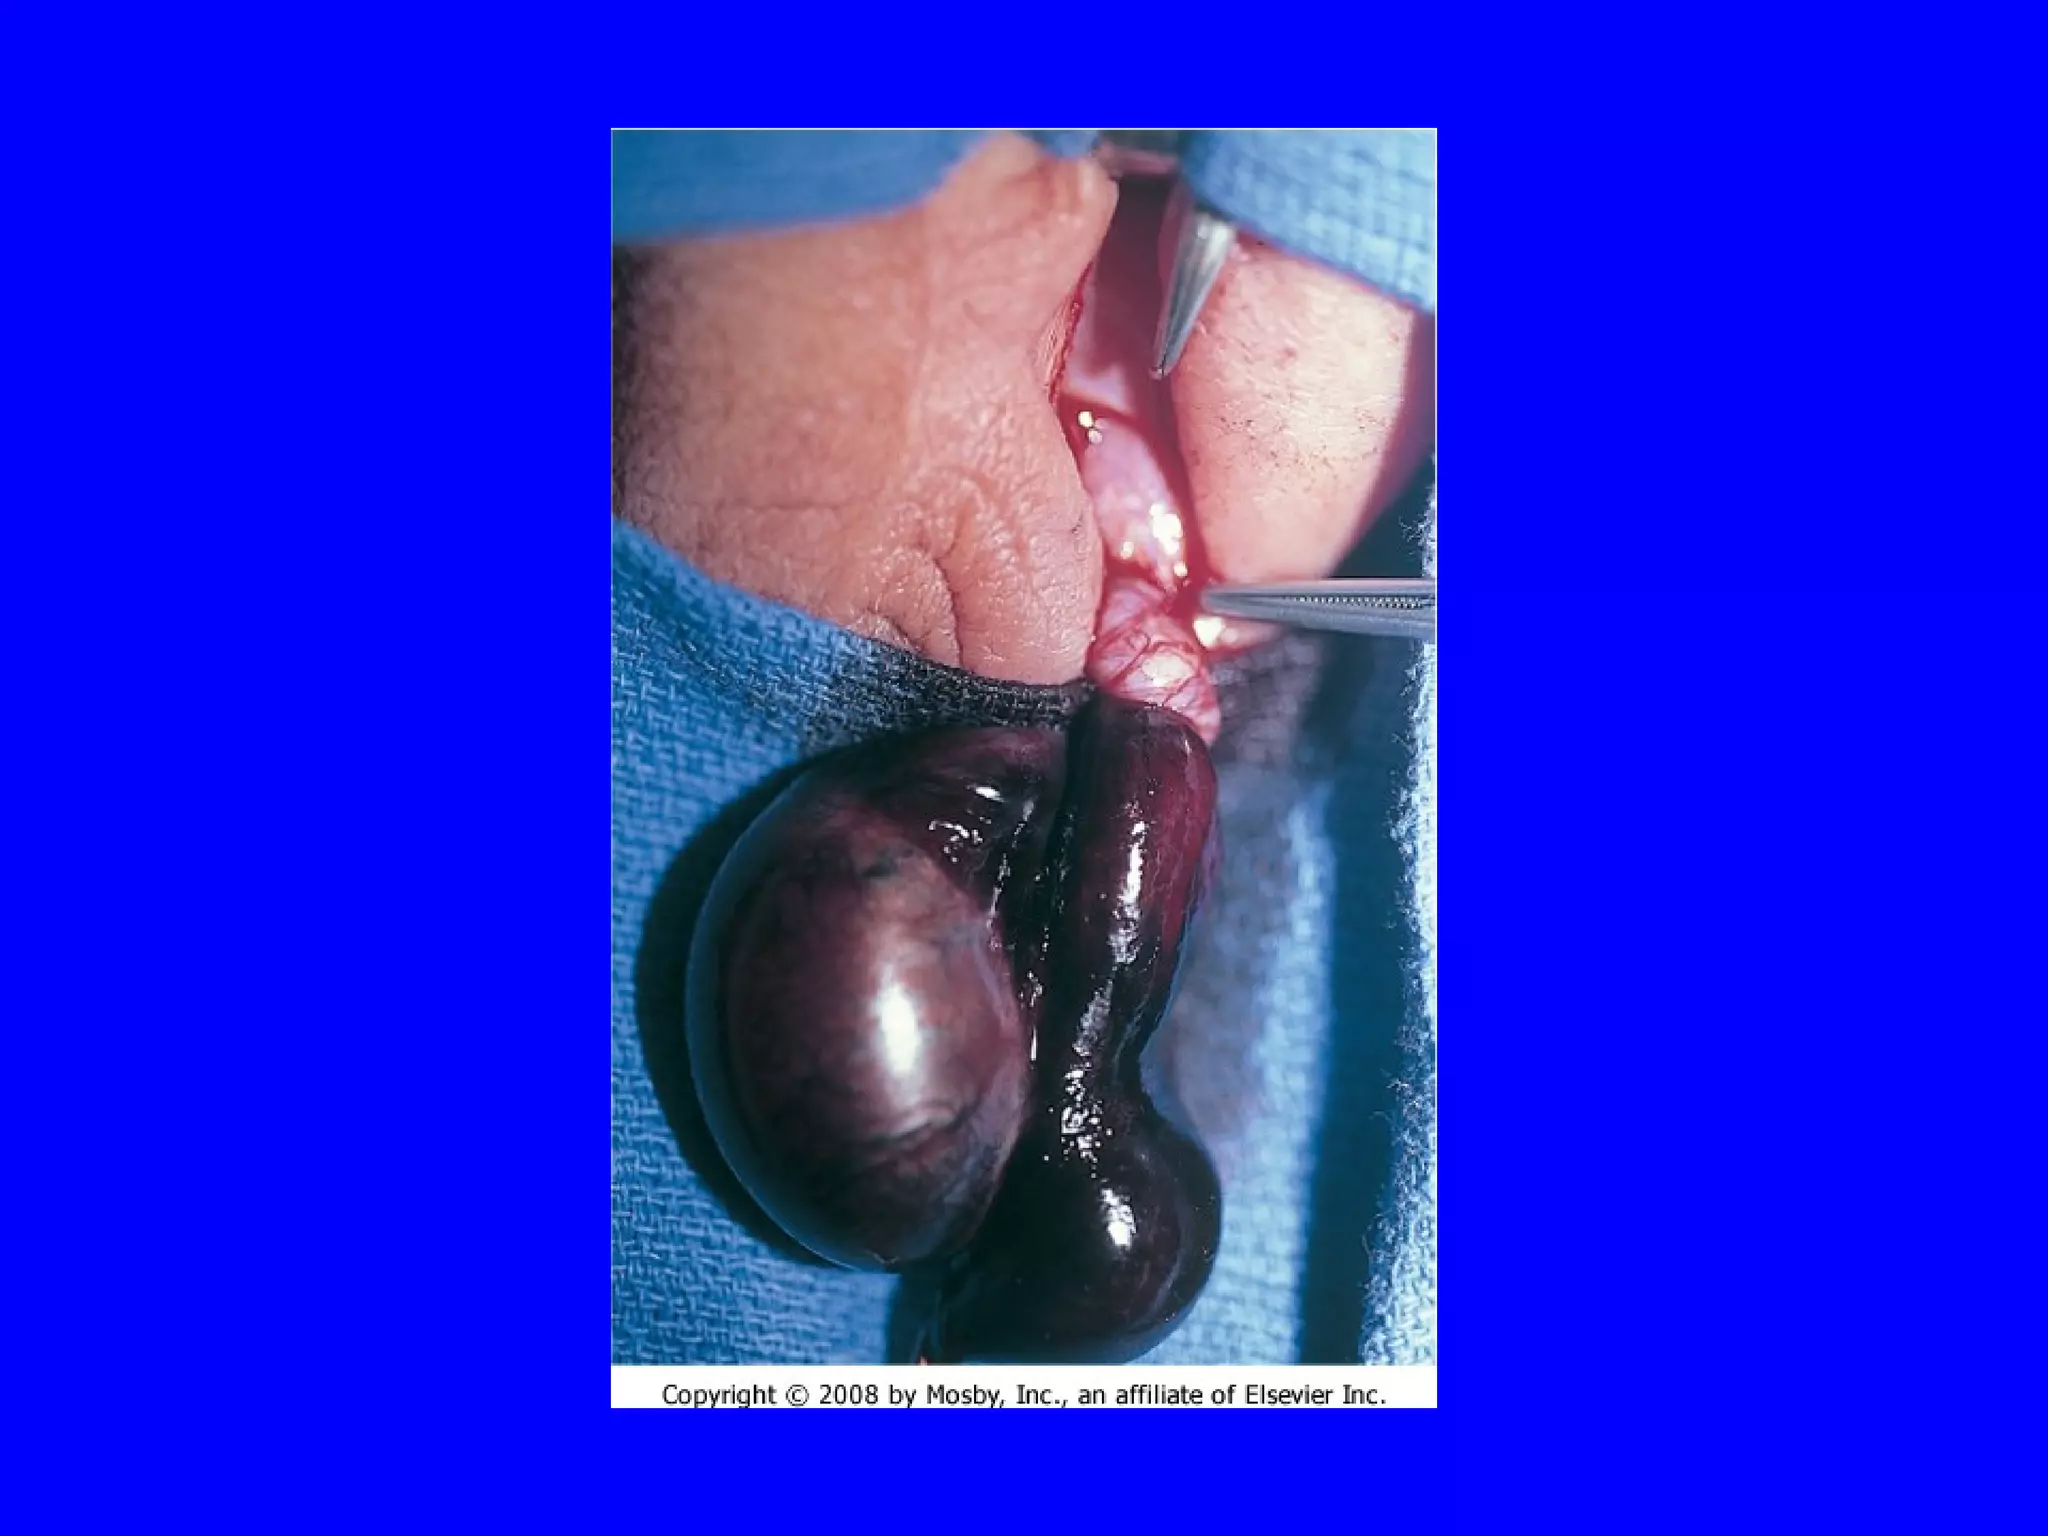

Testicular Torsion Testicular torsion occurs when a testicle gets twisted around, cutting off its blood supply.  The patient with this condition usually has severe pain in the testicle.  Due to inadequate fixation of the testes to the scrotum allowing for excessive movement Venous obstruction   edema   interrupted arterial flow   necrosis Clinically – Sudden acute testicular pain, scrotal swelling and very tender, absent cremastric reflex Dark purple color of the scrotum/testicle Diagnosis:  Ultrasound Nuclear medicine scan Treatment: Surgical detorsion If pain <4-6 hrs, can try manual detorsion 90% survival in testis torsion <6 hrs

Testicular Torsion Testiculartorsion occurs when a testicle gets twisted around, cutting off its blood supply. The patient with this condition usually has severe pain in the testicle. Due to inadequate fixation of the testes to the scrotum allowing for excessive movement Venous obstruction  edema  interrupted arterial flow  necrosis Clinically – Sudden acute testicular pain, scrotal swelling and very tender, absent cremastric reflex Dark purple color of the scrotum/testicle Diagnosis: Ultrasound Nuclear medicine scan Treatment: Surgical detorsion If pain <4-6 hrs, can try manual detorsion 90% survival in testis torsion <6 hrs